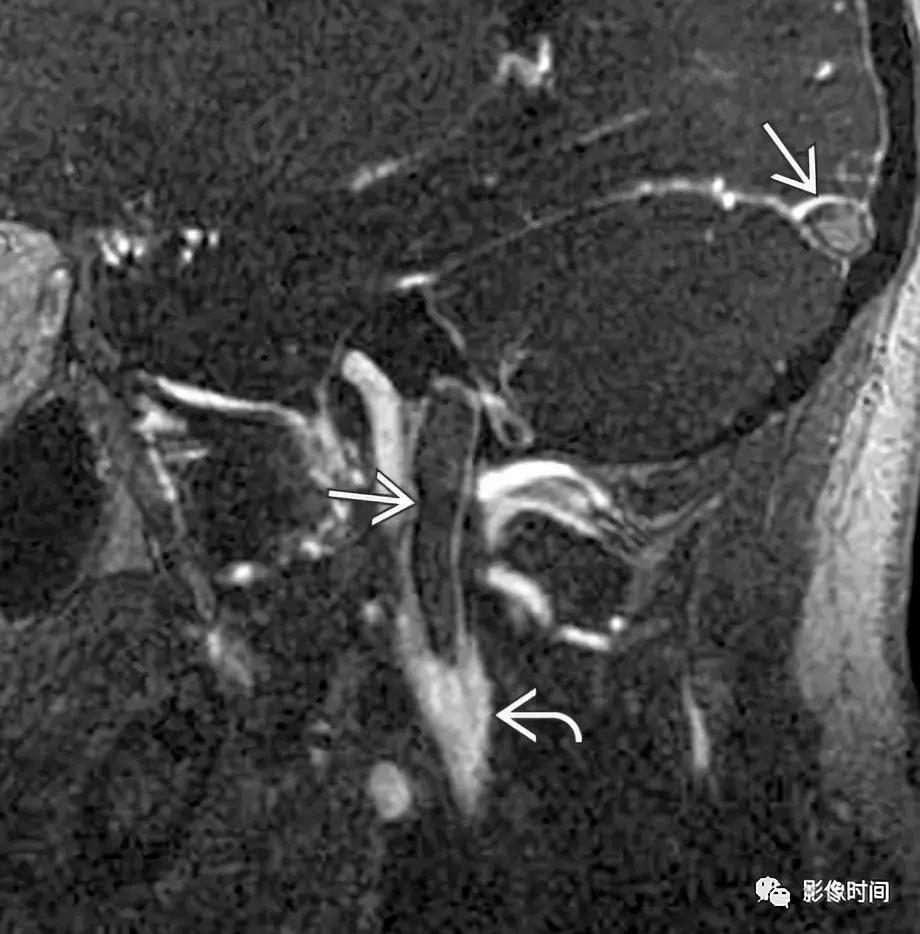

3、脑膜瘤:脑膜瘤是中枢神经系统最常见的脑外颅内肿瘤,大多数脑膜瘤发生在颅内。颈静脉孔区的脑膜瘤可向下延伸至颈动脉间隙。大多数脑膜瘤 CT 表现为等或者高密度,20% 钙化,邻近骨质表现为反应性骨质增生。在 MRI 上,脑膜瘤通常表现为 T1WI 等或稍低信号,T2WI 等或稍高信号,明显强化,可见脑膜尾征。

轴位 CT 显示病灶相邻的骨质增生(白色箭头),正常左乳突骨皮质 (黑箭头)。轴位 T2WI 病灶呈等信号 (白色箭头),向前推移颈内动脉 (i)。左侧颈内动脉的正常位置也被观察到。

矢状位 T1WI+C 病灶明显强化 (白色箭头) 从后窝延通过颈静脉孔 (黑色箭头) 延伸至右颈动脉间隙,见硬膜尾征(无尾箭头)。